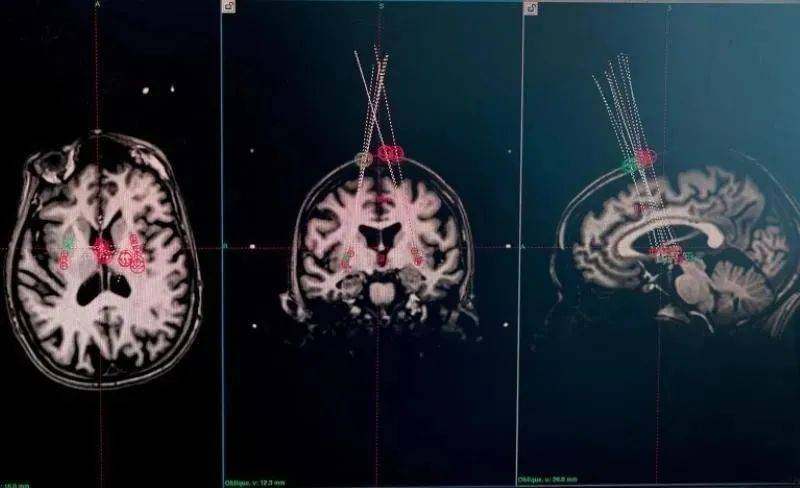

▲瑞典斯科讷大学医院科学家利用一根针头,将细胞移植到人脑中,以治疗帕金森病。图片来源:英国《自然》

▲科学家根据脑部MRI扫描图像确定针头将细胞送往何处。来源:英国《自然》网站